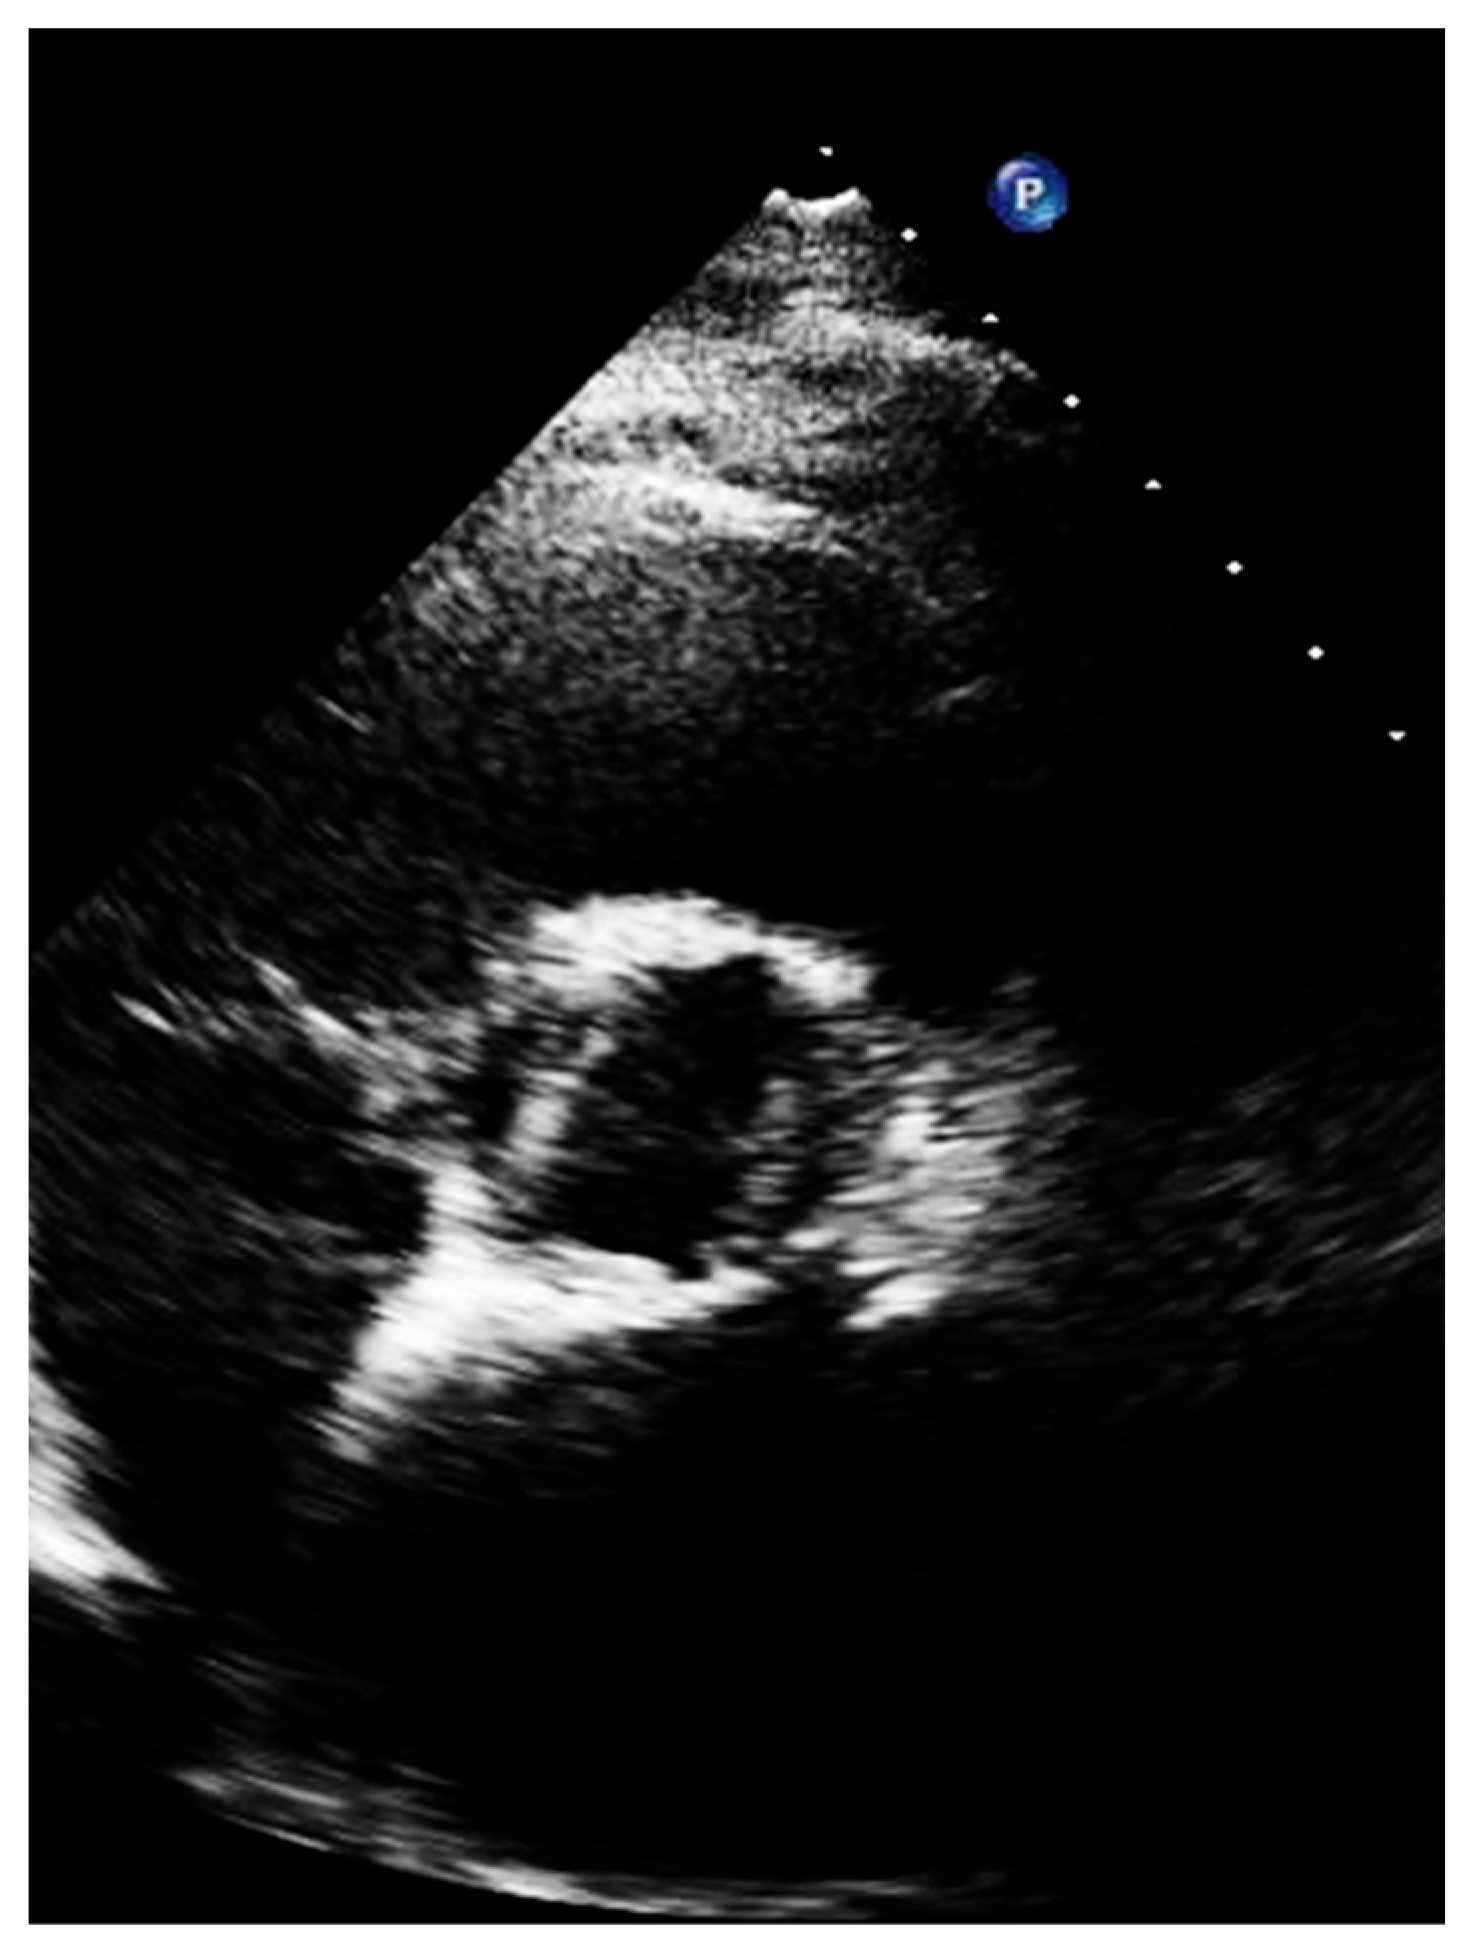

Figure 2. Incorrect long-axis view.

Transthoracic echocardiography should be initiated with the long-axis view [12]. From this view, we can measure the left ventricular outflow tract (LVOT) and begin assessing the morphology and movement of the aortic valve [13,14]. Importantly, sonographers should optimize the long axis as more perpendicular to the aortic posterior wall and to the anterior septum so that the lowest angle between the aortic wall and the anterior septum is reached. Figure 2 reports what should be avoided during long-axis acquisition.